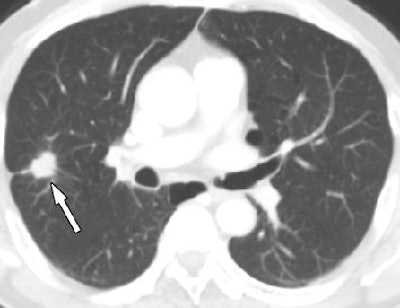

| Axial cardiac CT images in a 63-year-old man with solitary pulmonary nodule visible in full field-of-view only. Above, full-FOV image shows 2-cm spiculated nodule (arrow) in right upper lobe. Below, limited-FOV image obtained at same level shows nodule is collimated from view. This lesion was confirmed to be adenocarcinoma after right upper lobectomy. Images republished with permission of the Radiological Society of North America from Radiology (Vol. 255:2, pp. 369-376). |

The mean diameter of the cancers was 23 mm ± 10.5 (range, 5-42 mm), and the most common location was the right upper lobe (n = 13, 36%). Adenocarcinoma was the most common histology, seen in 86% of patients (31 of 36) with lung cancer. Of the 34 non-small cell lung cancers detected at CT, 23 (68%) were resectable, including 16 of the earliest stage IA cancers, the authors wrote.